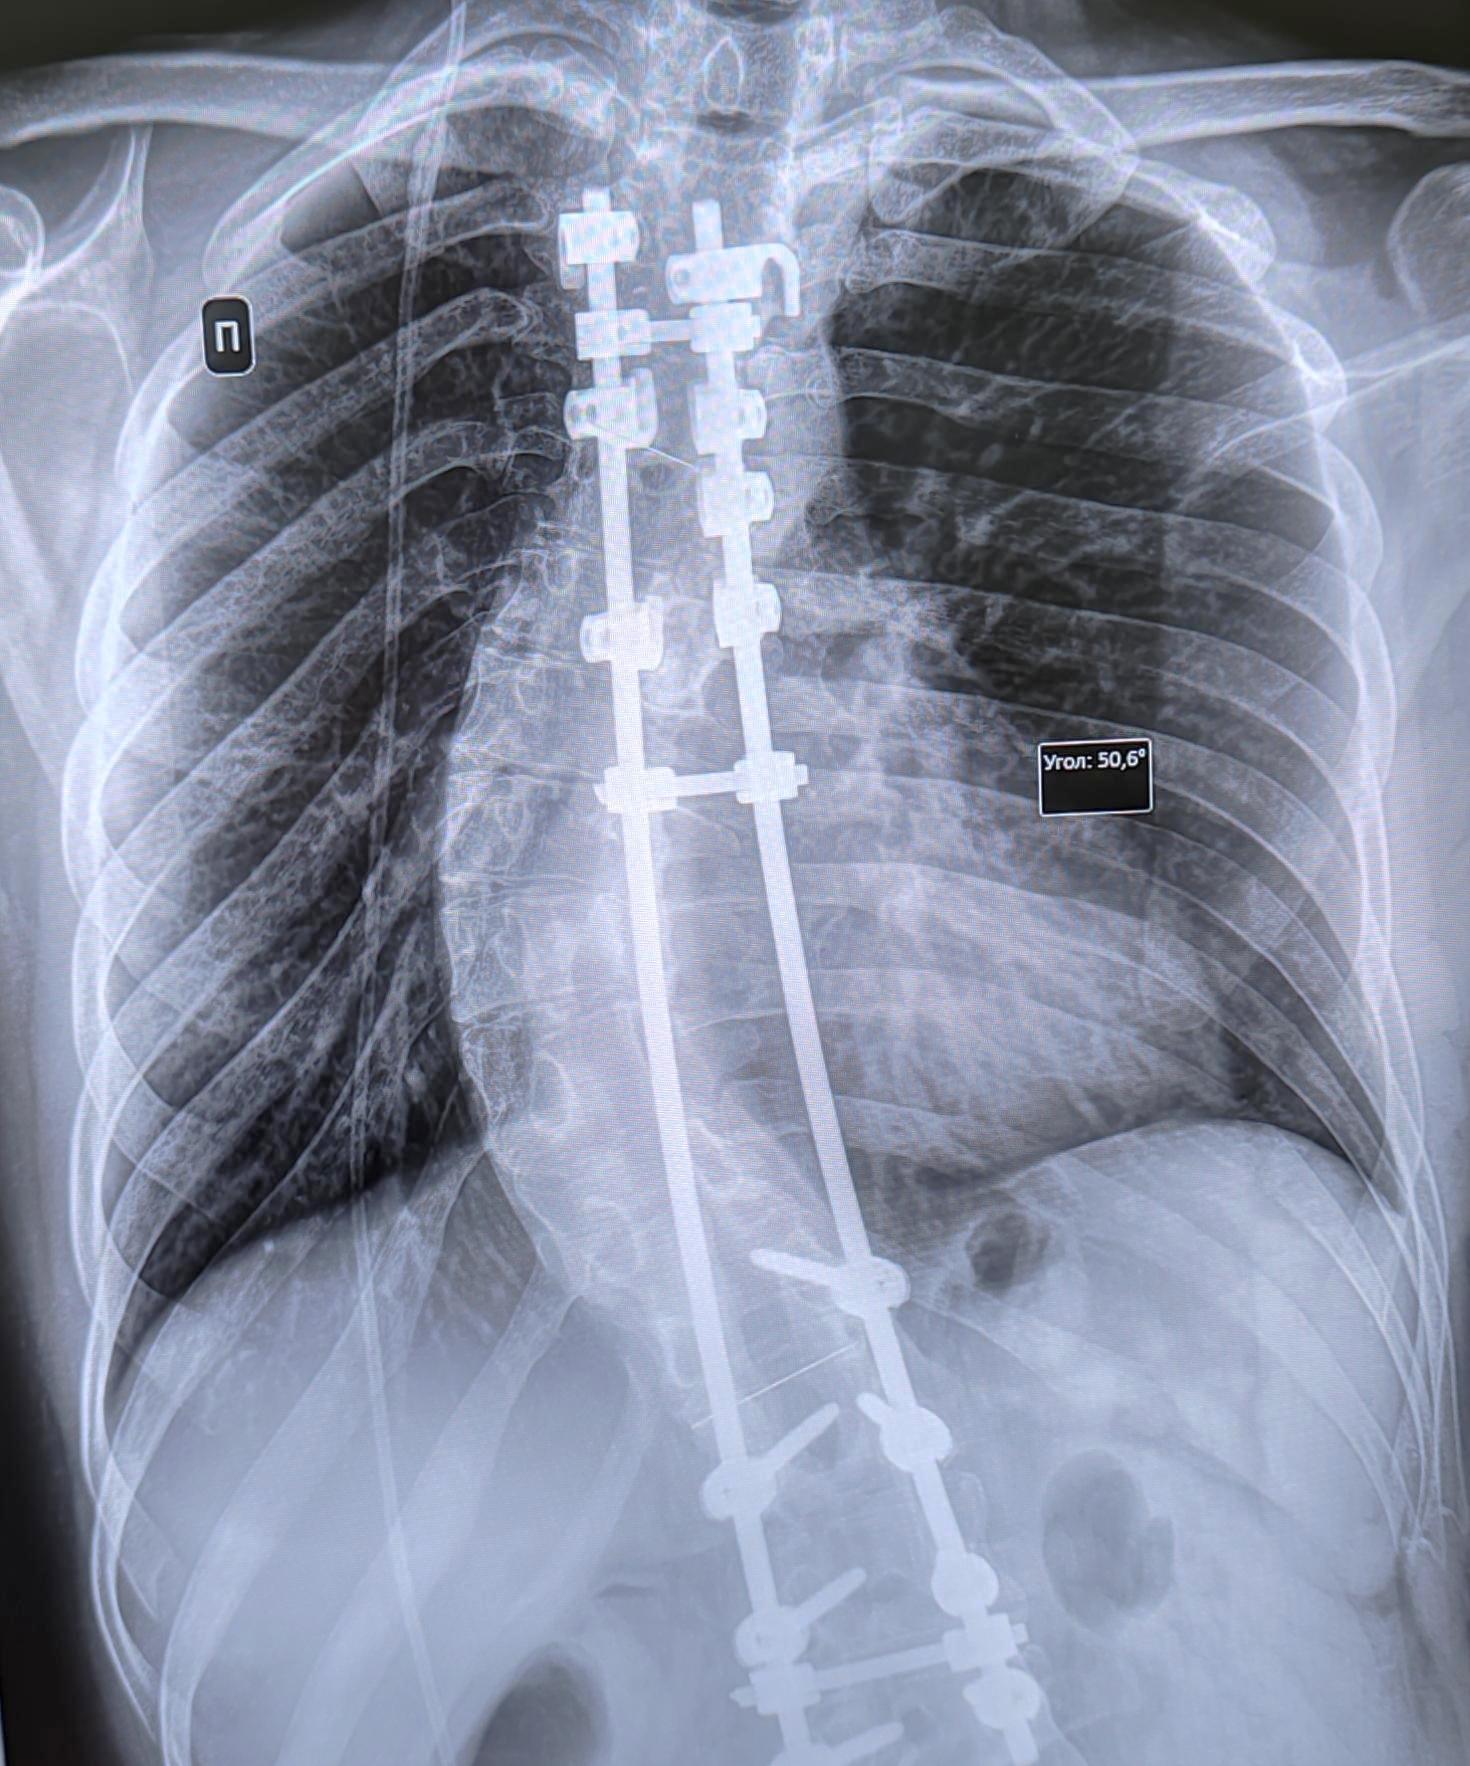

Сколиоз IV степени

Выраженная ротация, торсия тел позвонков грудо-поясничного отдела позвоночника, визуализируется правосторонняя сколиотическая дуга с вершиной на Th8-9,с углом девиации 50.6 градусов, в условиях установленной металлоконструкции для коррекции сколиотической деформации с транспедикулярной фиксацией в Th12-L3 позвонках, резорбции костной ткани вокруг металлоконструкции не выявлено. Заключение: Правосторонний сколиоз грудо-поясничного отдела позвоночника 4 (четвертой )ст. в условиях корригирующего МОС.

Категория годности с диагнозом сколиоз 4 ст. по статье 66(Болезни позвоночника и их последствия:)а-Д(не годен к военной службе) по I, II, III графам.